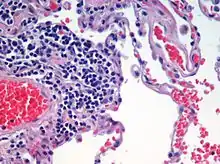

La coloration de tissu biologique est souvent nécessaire pour la mise en évidence et l'identification de cellules ou de la structure tissulaire. Certaines colorations sont compatibles avec la vie cellulaire, d'autres nécessitent la fixation des tissus, et parfois la création de coupes histologiques.

Colorations topographiques

Un colorant consiste souvent en une solution aqueuse contenant un composé portant des groupements chimiques chargés électriquement (fonctions anioniques ou cationiques) et qui peut colorer une ou plusieurs substances de manière stable.

Constitué d'un groupement chromophore (couleur) et d'un groupement auxochrome (groupement ionisé): fixation permanente sur des groupements acides ou basiques des constituants cellulaires (à un pH donné).

Caractéristiques :

- non spécifique d'un type de molécule ;

- donne une vue d'ensemble du tissu : renseigne sur la répartition, l'architecture et la structure des cellules ;

- résulte de l'action conjuguée d'un colorant acide (éosine) et d'un colorant basique (hémalun, bleu de méthylène).

Les substances acides (chargées -) de la cellule sont colorées par un colorant basique (chargé +), les substances basiques (chargées +) de la cellule par un colorant acide (chargé -).[pas clair]

Cette coloration colore un type de charge. On peut voir la morphologie de la cellule (forme), la position du noyau et sa forme. Ainsi, on peut déterminer le nombre de types cellulaires dans le tissu et la structure de ce tissu (cellules collées ou non).